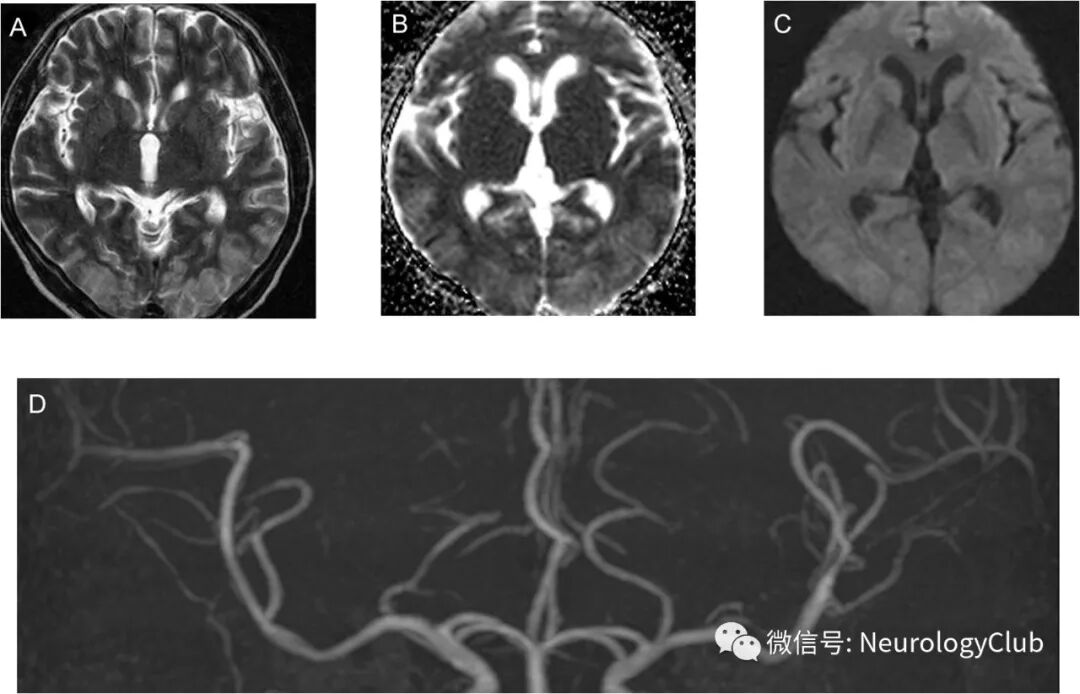

52岁男性,因扩张型心肌病所致终末期心功能衰竭行心脏移植。术后第8天,患者出现全面强直-阵挛发作。发作间期脑电图未见明显异常,实验室检查无殊。行头颅MRI和MRA检查。可见大脑半球后部多发T2高信号病灶。未见急性脑梗死或颅内血管异常(图1)。考虑为他克莫司治疗所致的PRES。为避免病情恶化,将他克莫司减量维持在正常血药浓度下限。此外,严格控制血压防止脑水肿加重。数小时后患者完全恢复。术后第18天,患者出现意识状态改变伴双侧肌力下降(2级)。影像学提示双侧额顶枕叶新发急性梗死以及多处脑血管弥漫狭窄(图2)。行DSA检查提示经典的脑动脉腊肠样外观,是RCVS的特征性改变(图3A)。实验室检查无血管炎相关证据。停用他克莫司,并给予尼莫地平治疗。患者血管痉挛较前改善(图3B)。左上肢肌力恢复至3级。随访3月,影像学未见新发梗死和血管收缩改变,但肢体肌力尚未完全恢复伴视敏度下降。

(图3:A:DSA可见右侧颈内动脉[ICA]远端多分支血管收缩;B:治疗后复查收缩血管较前改善)